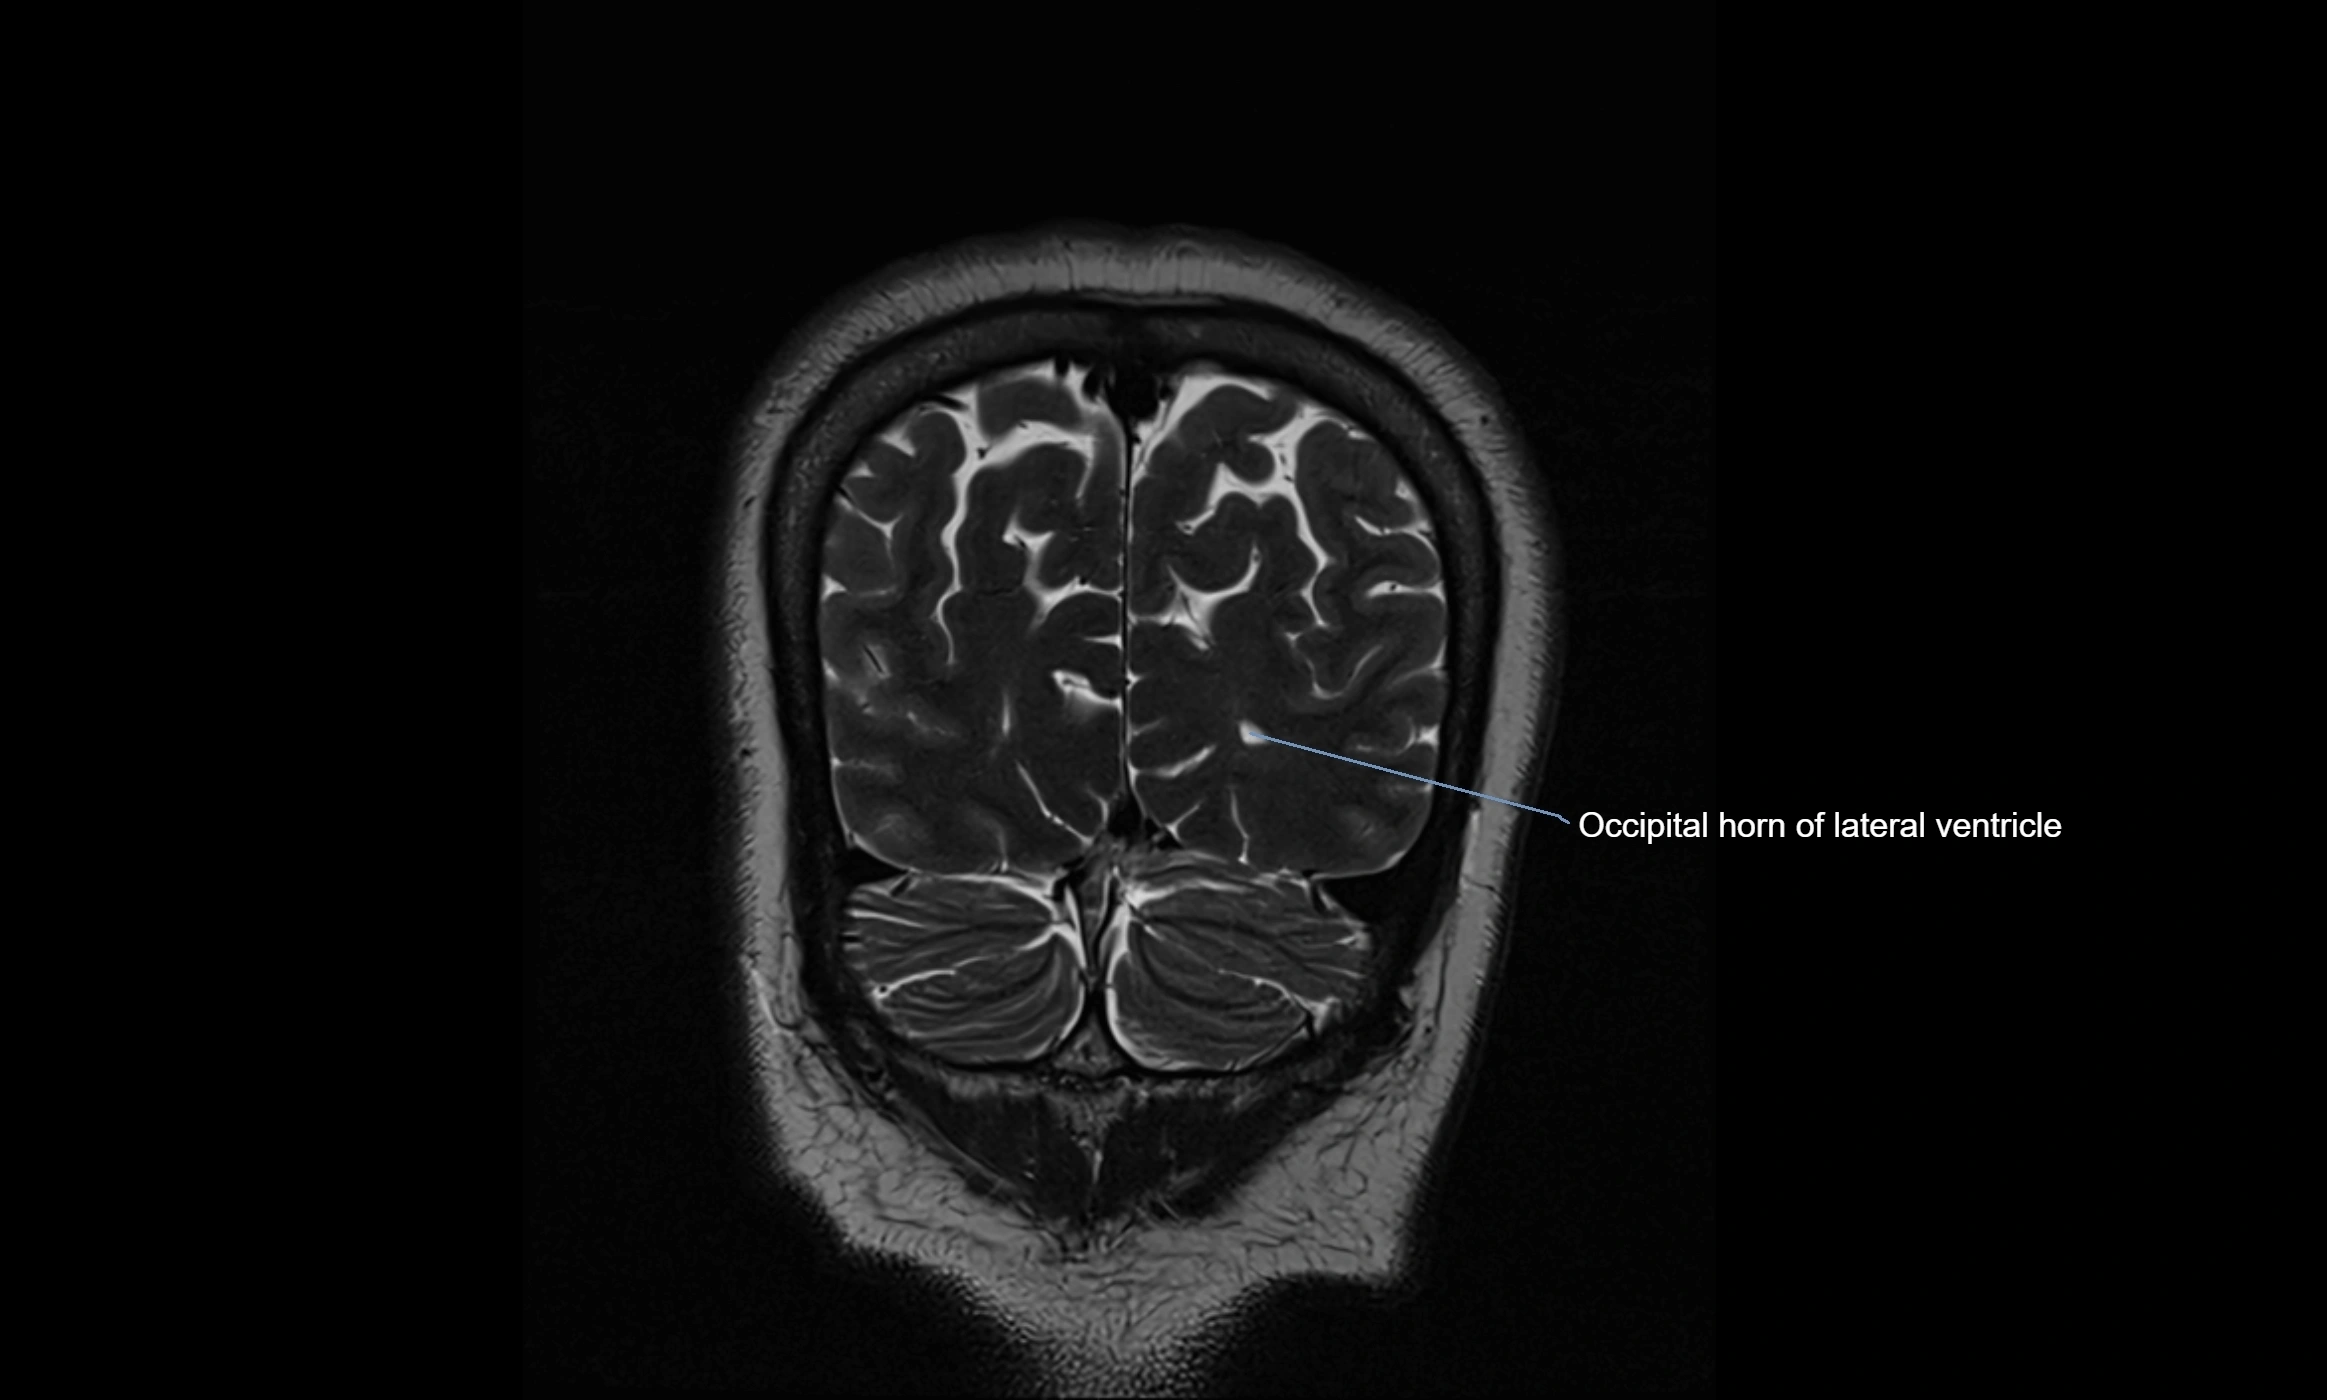

MRI images

image